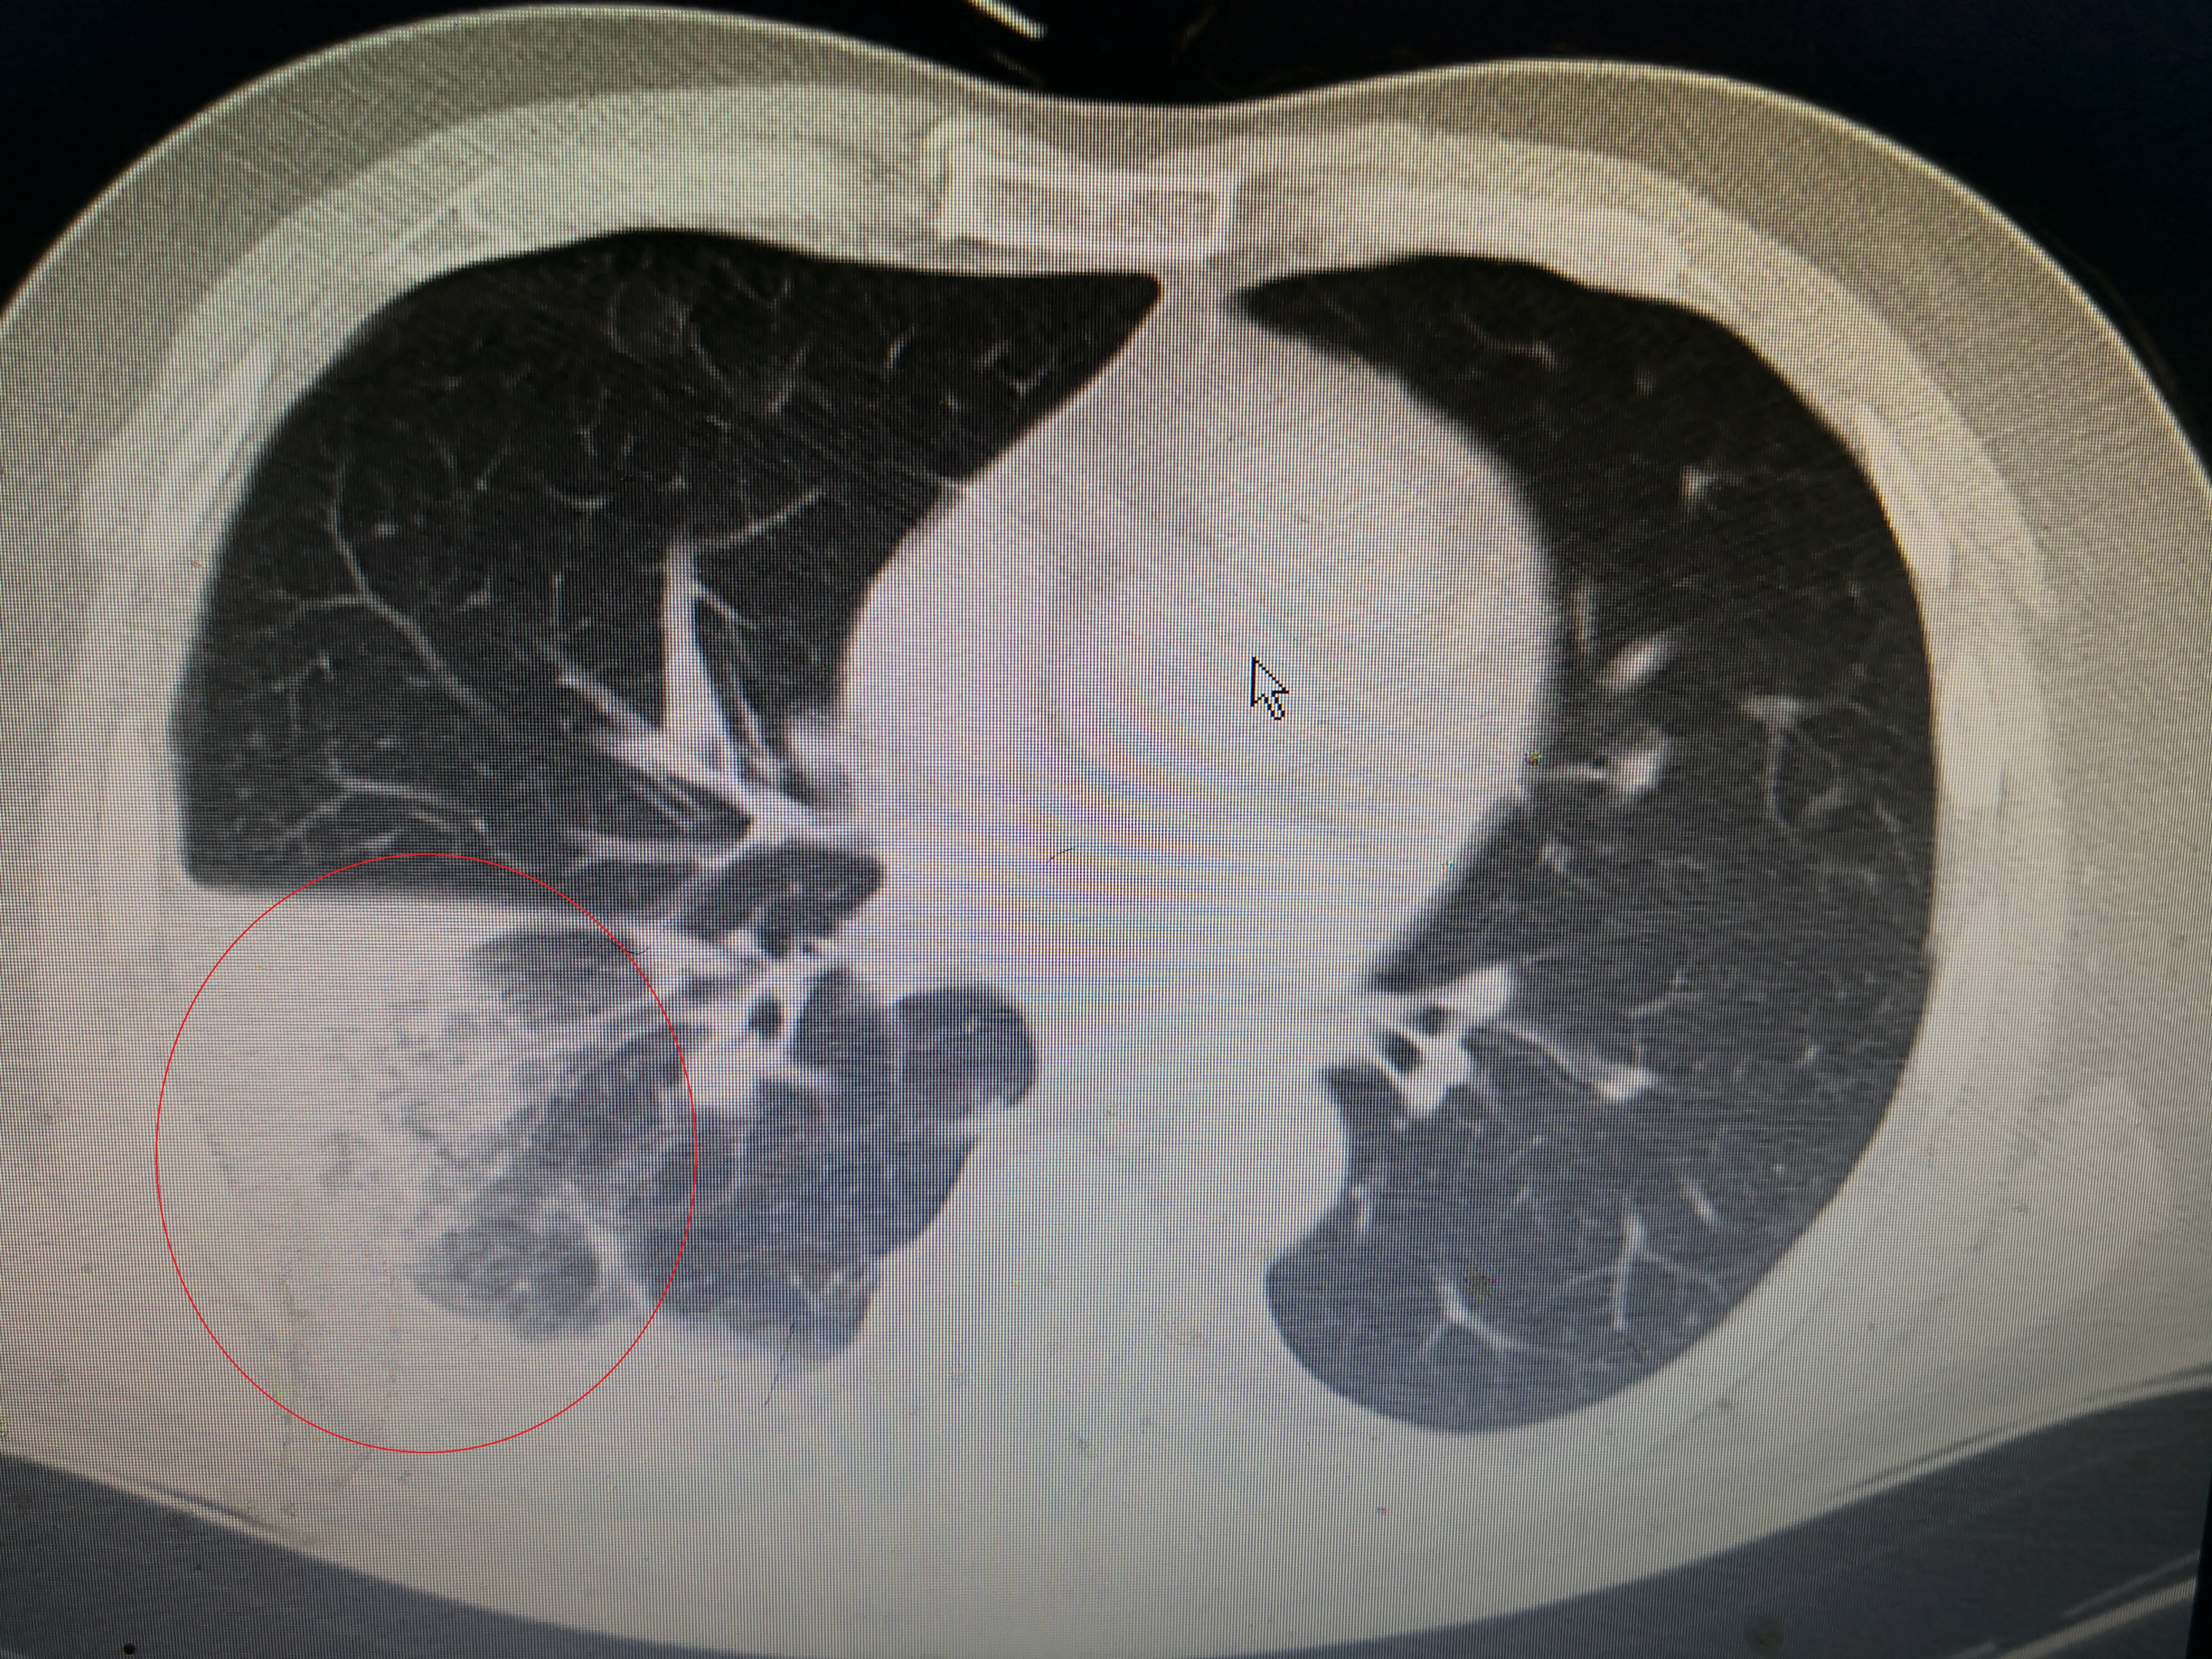

下面这个患者就是近期从西城院区转过来的发热,大片肺炎患者。患者男,55岁,因发热3天到西城院区就诊,体温最高41℃,伴有畏寒、乏力、纳差,咳嗽少痰,伴有顽固性呃逆,没有新冠肺炎流行病学史,但是CT提示右肺大片炎症,在发热门诊隔离抗炎,经两次筛查阴性,但是抗炎效果不佳,仍有高热,转到这边急诊二病区抗炎治疗。

该患者没有既往病史,没有新冠流行病学史,没有用药史,有典型的发热、咳嗽症状,CT提示右肺炎症。

化验白细胞15.48×10^9明显升高,C反应蛋白108mg/l升高,符合经典的社区获得性肺炎标准,所谓社区获得性肺炎(CAP),说白了就是在医疗机构以外得的肺炎,相对来说肺炎链球菌、支原体等多见,耐药性少见。该患者白细胞和C反应蛋白升高符合细菌感染表现,而且血气氧分压65mmHg,明显低氧,接近于I型呼吸衰竭,属于重症肺炎。